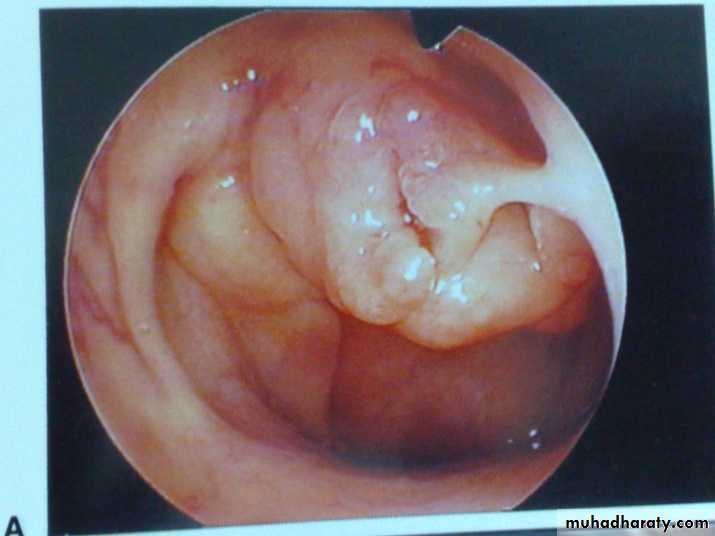

Is a vascular tumour of the nasopharynx occurring almost entirely in adolescent males (7-19 years with a mean of 14 years. The tumour has a tendency to regress after puberty. Although the tumour is benign, but it is locally invasive and behaves as malignant.

Juvenile Nasopharyngeal Angiofibroma

Microscopically, the tumour consist of vascular spaces abounding in a stroma of fibrous tissue. The vascular spaces consist of thin-walled sinusoidal vessels unsupported by a muscular coat. This account for the severe bleeding as the vessels loose the ability to contract.Clinical Picture

The patient is nearly always a young boy with a mean age of 14 years.1. Repeated attacks of epistaxis which can be extremely profuse due to absence of muscular coat from the sinusoids.

2. Progressive nasal obstruction.

3. Conductive deafness occurs from pressure on the Eustachian tubes.

Examination

1. Endoscopy and posterior rhinoscopy: smooth, rubbery lobulated mass in the nasopharynx.

2. Middle ear effusion.

3. Mass in the nasal cavity or on the cheek if the tumour has extended anteriorly or laterally.

4. Proptosis results from extension of the tumour to the

orbit through the

infraorbital

fissure.